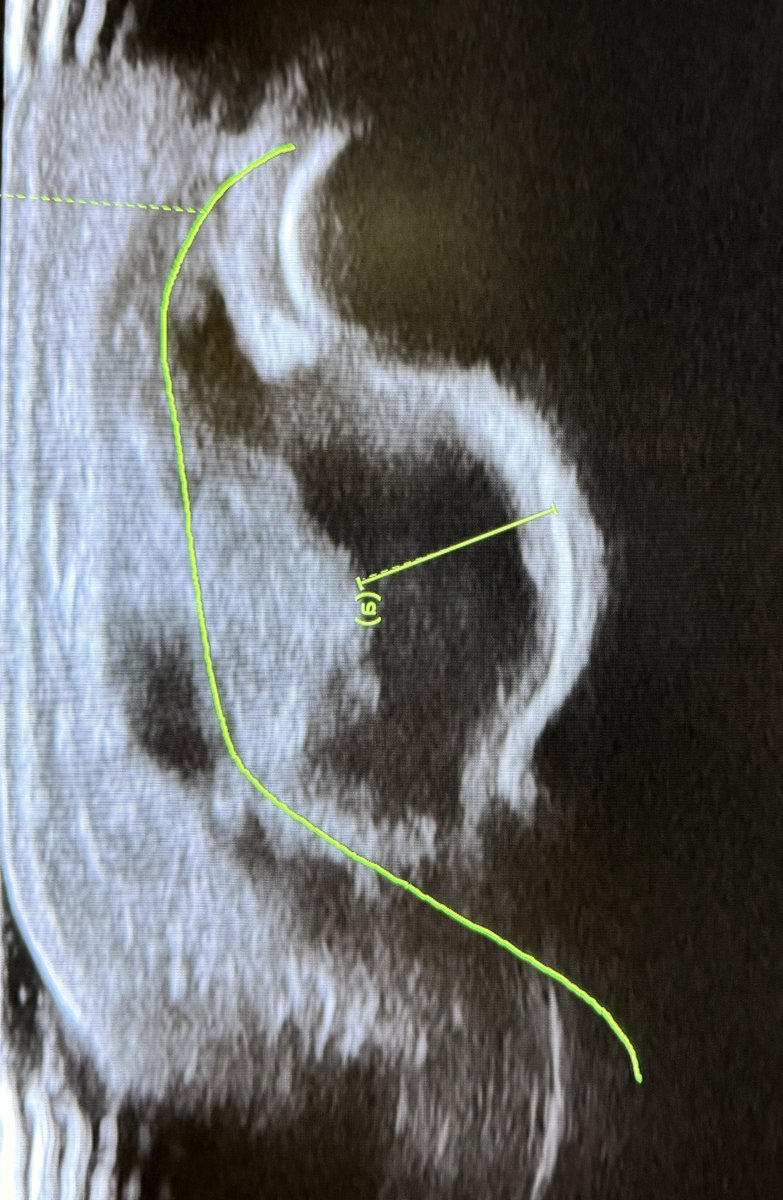

Double contour sign! It is a sonographic sign specific for gouty arthritis. Why does it occur? In gout, monosodium urate crystals deposit on the surface of the hyaline cartilage within the joint. This results in two distinct echogenic lines: 1.Deep line = normal

Double contour sign!

It is a sonographic sign specific for gouty arthritis.

Why does it occur?

In gout, monosodium urate crystals deposit on the surface of the hyaline cartilage within the joint.

This results in two distinct echogenic lines:

1.Deep line = normal